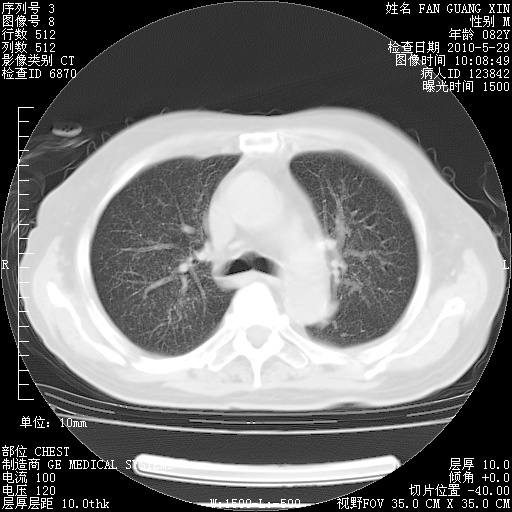

再治疗10天后的肺部CT

再治疗10天后的肺部CT 纵膈窗